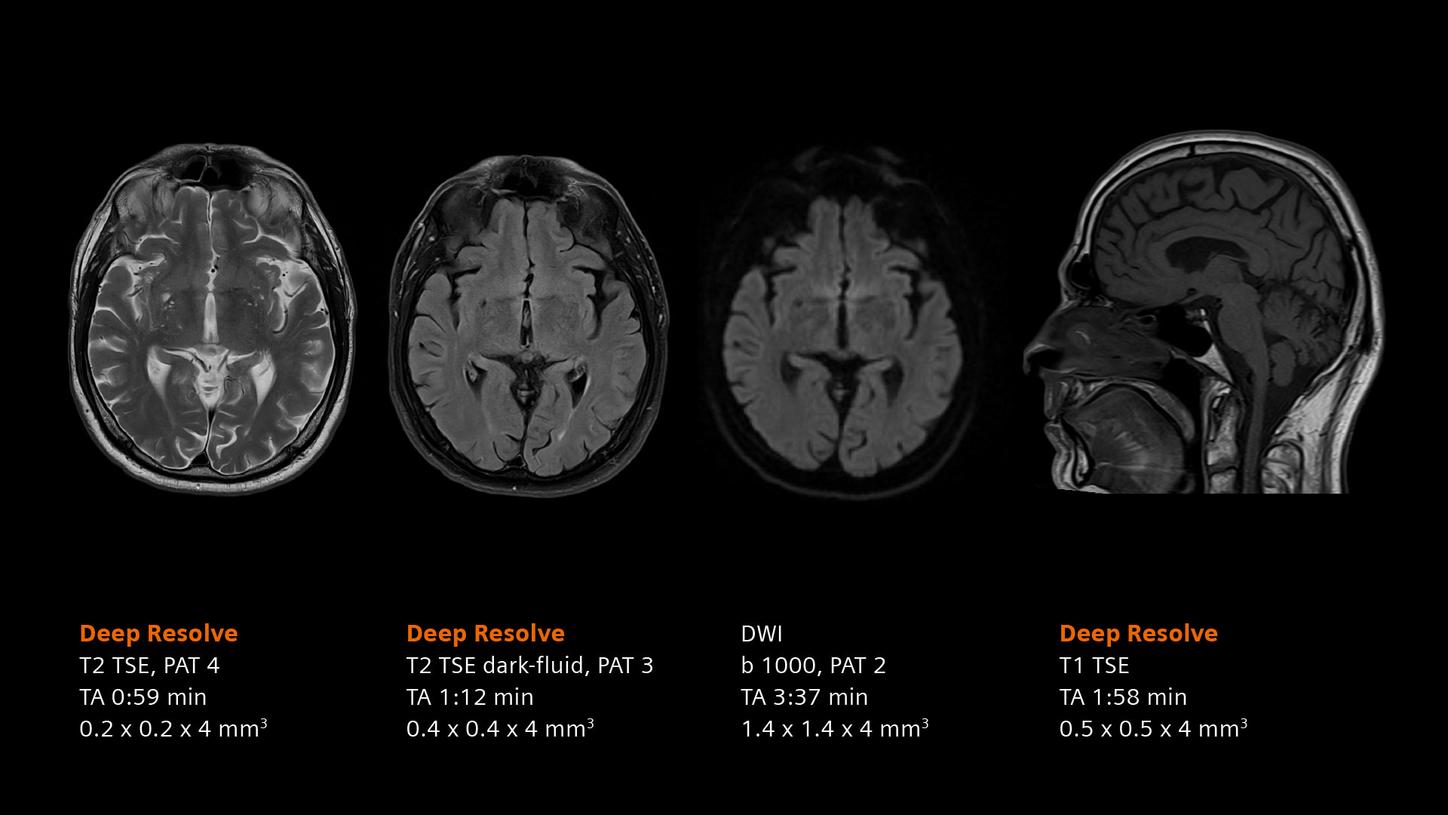

Deep Resolve will be at the forefront of the revolution in MRI acceleration. Deep Resolve will enable our fastest MRI, with images that will have extraordinary clarity, higher clinical productivity, and an even better patient experience. This transformational effect of Deep Resolve is now planned to expand to 3D5, unlocking a new dimension in MRI image resolution and speed.